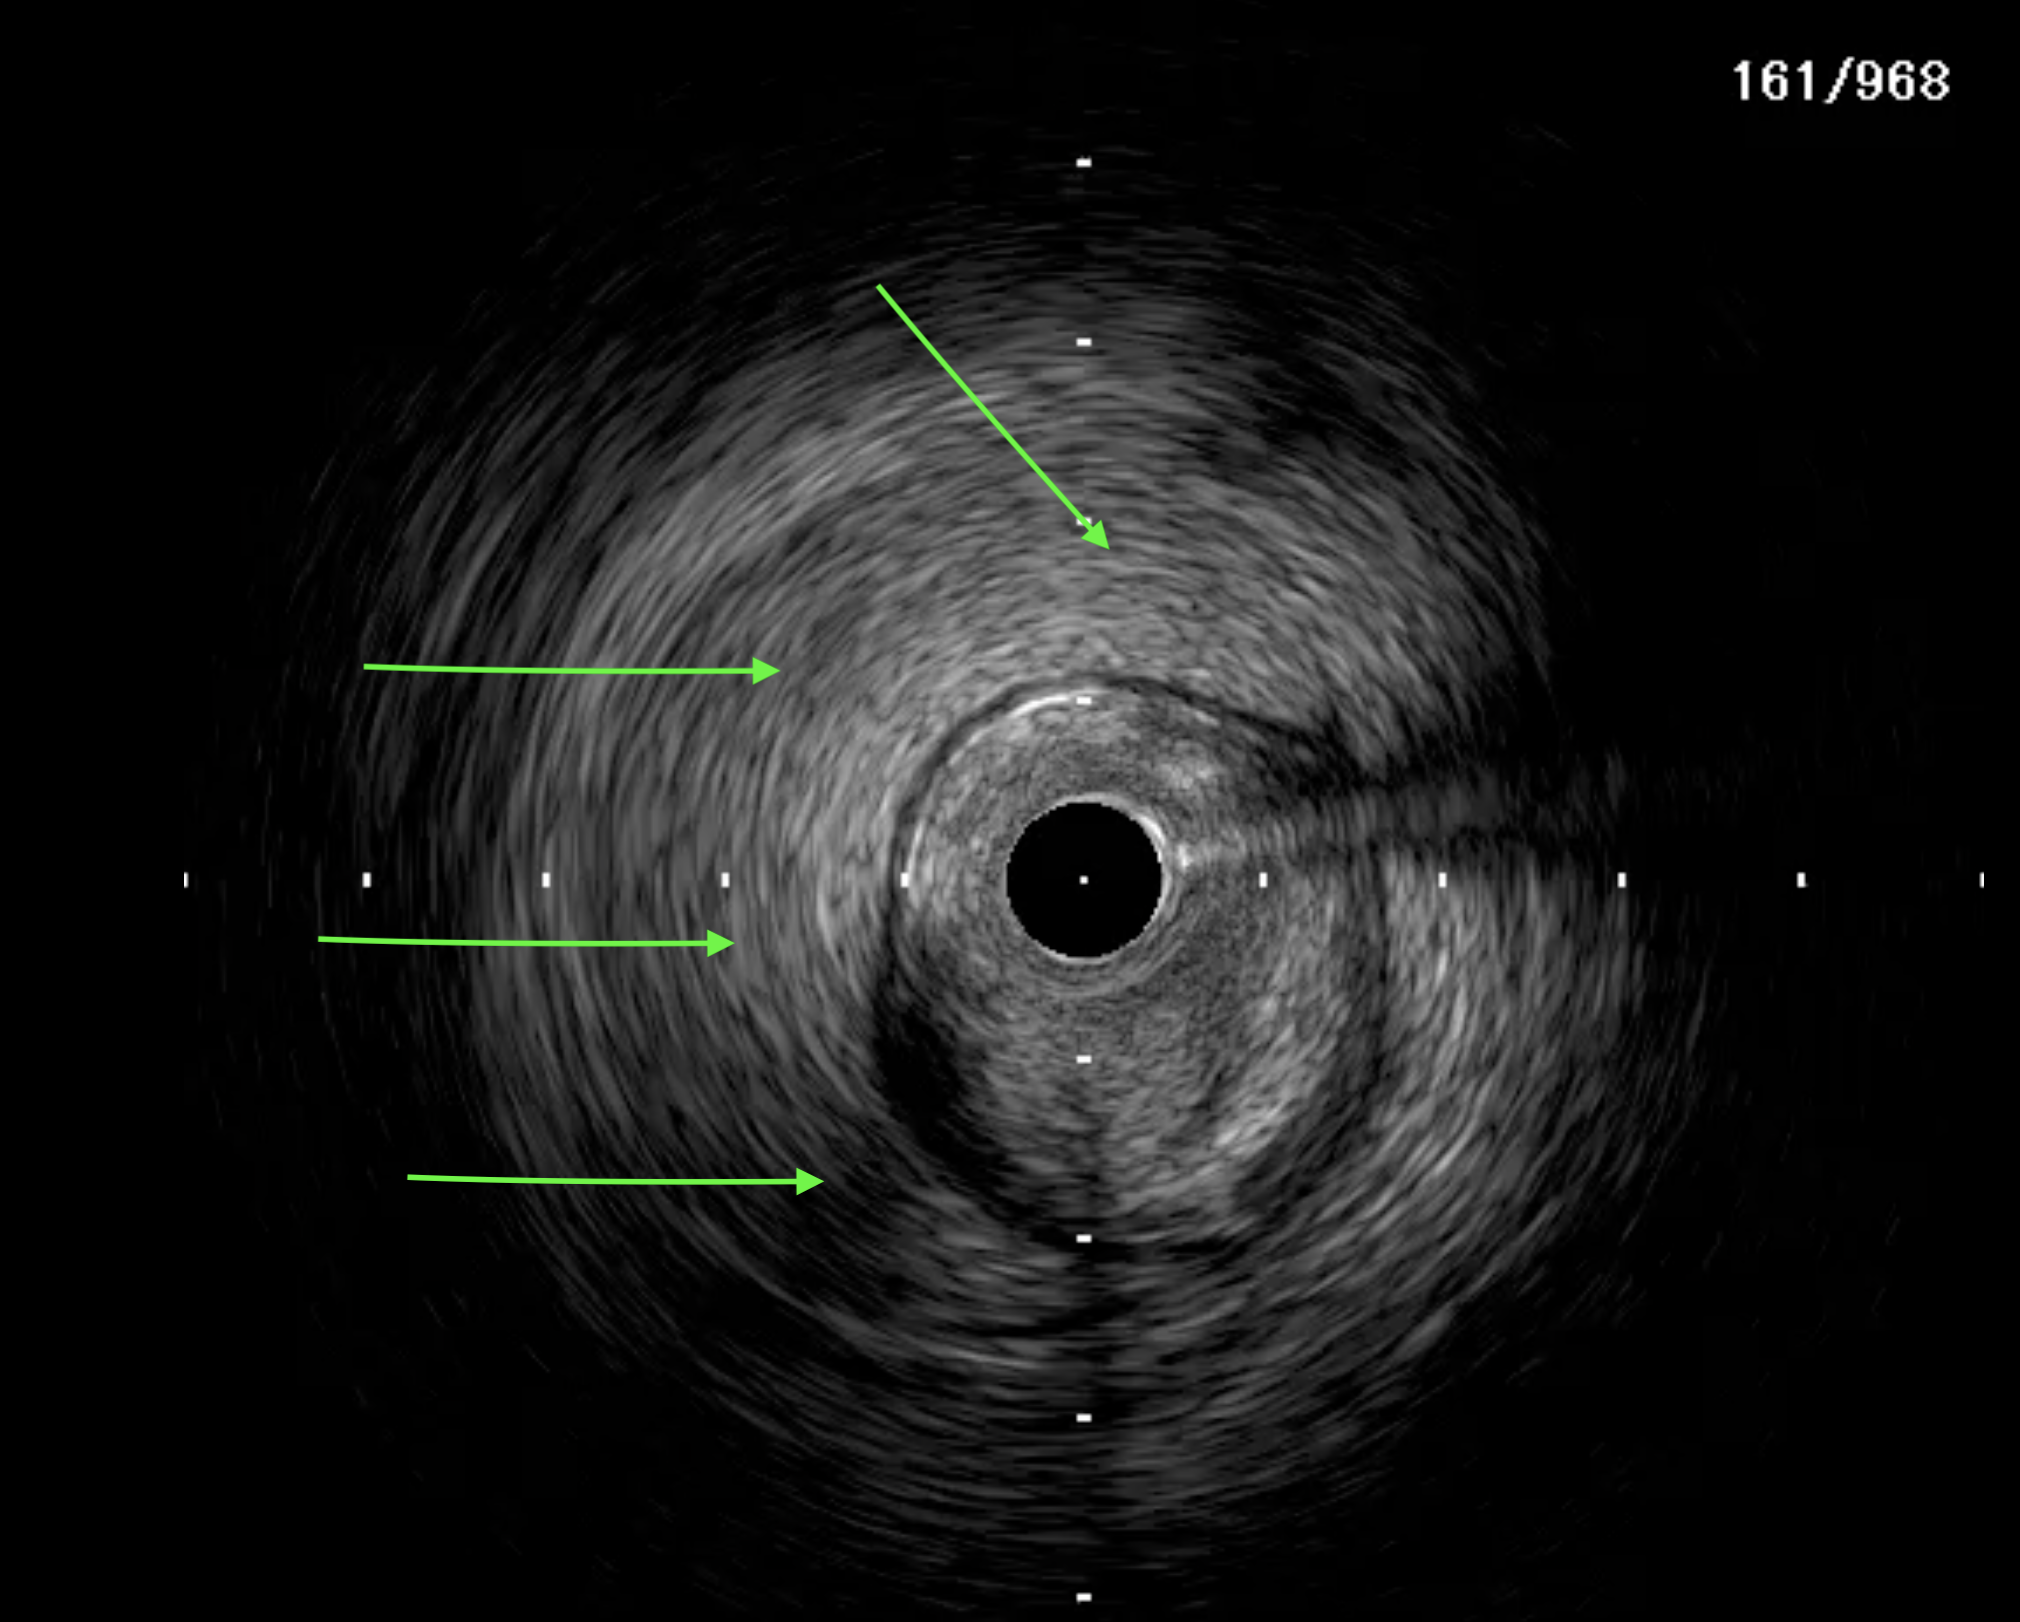

A 51-year-old man presented with stable angina and previously failed right coronary artery (RCA) CTO PCI. During RCA CTO PCI (Figure 1), the wire was inserted into the extraplaque space (Figure 2, Video 1). Intravascular ultrasound (IVUS) showed a hematoma (Figure 3A, Video 2). Live 3-dimensional tip detection IVUS wiring was successful (Figure 4, Video 3). A FineCross microcatheter (Terumo) was placed over the first wire into the extraplaque space and blood was withdrawn by connecting a negative indeflator to the microcatheter. Stents were deployed (Figure 5) and postdilated. Post-IVUS showed almost complete resolution of the hematoma (Figure 3B, C; Video 4) with good results (Figure 6, Video 5).